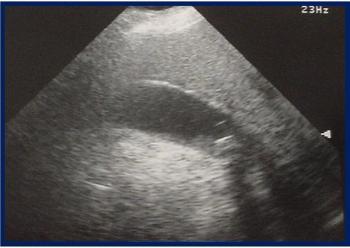

What do the symptoms and ultrasound image associated with the patient's pain suggest? Would you discharge her to home?